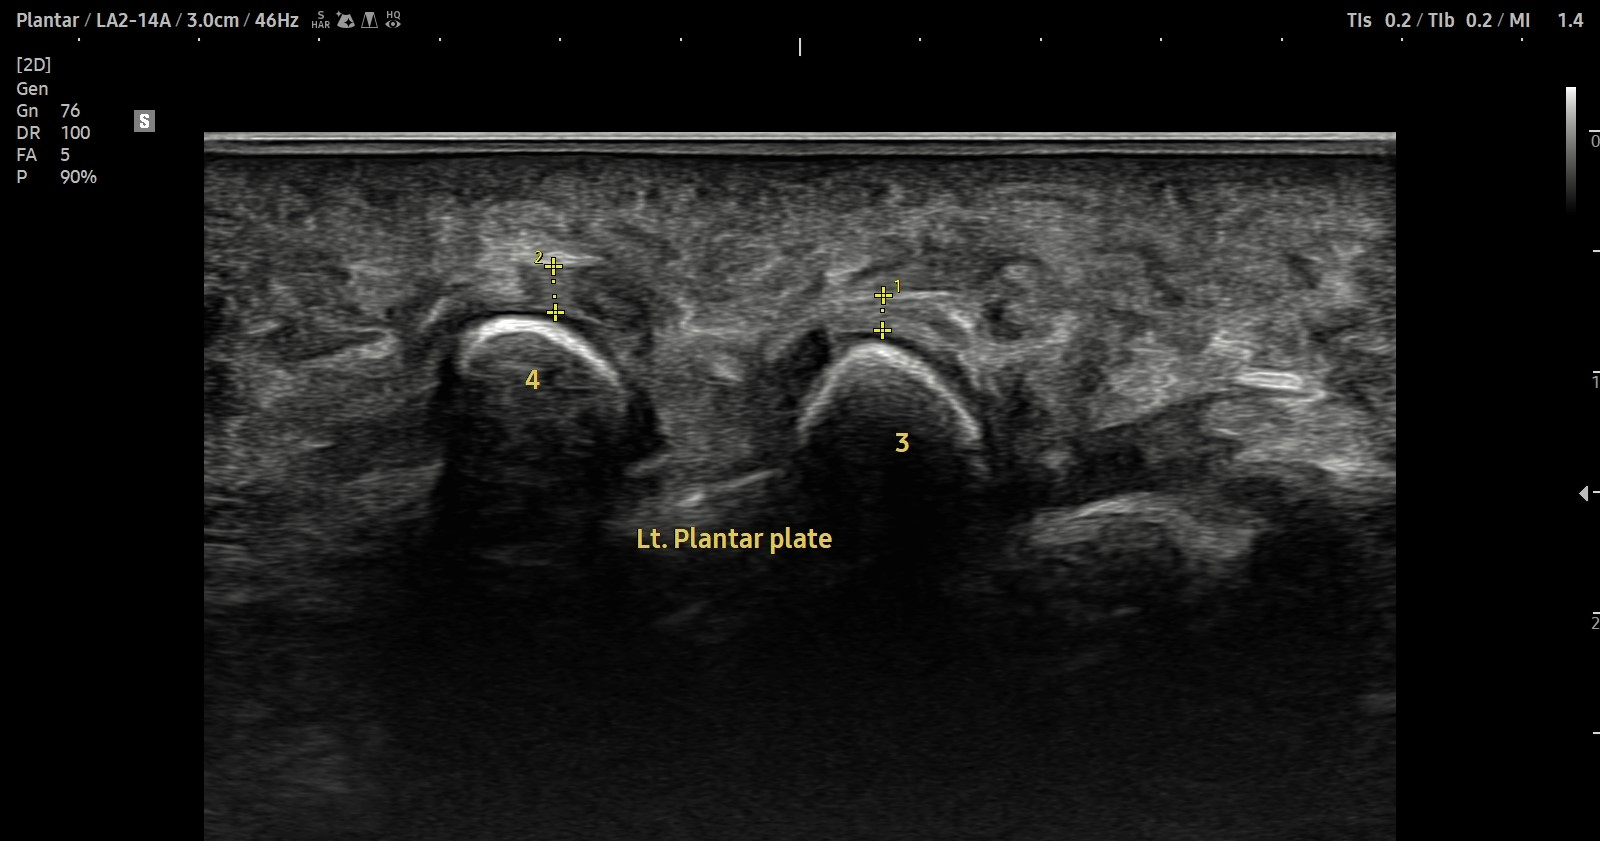

- 치료기간 : 2025. 7 . 4 ~ 2025 . 9 .1

- 치료횟수 : 10 회 (2cycle)

치료 전

치료 후